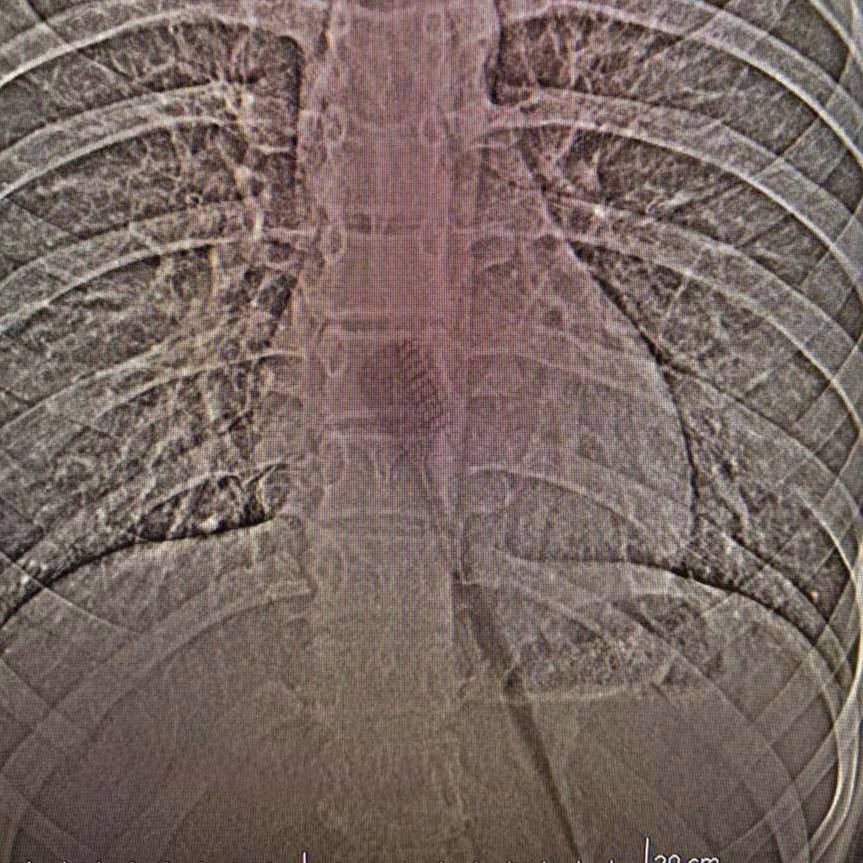

Первичный осмотр в местной поликлинике выявил серьезную проблему, и ребенка экстренно госпитализировали в республиканскую детскую клиническую больницу. После проведения рентгенографии и компьютерной томографии (КТ) медики смогли точно определить местоположение инородного тела. Обнаружение 19-сантиметровой пластиковой щетки, которая представляла значительную угрозу перфорации стенок желудка или кишечника, потребовало немедленного хирургического вмешательства.